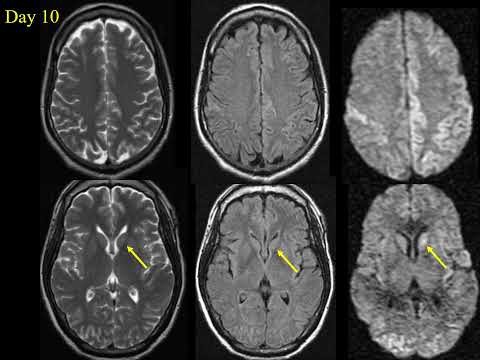

Prion Diseases Kucharczyk Neuroradiology Nov 2021

Grand Rounds. A clinical update on Prion Disease. Dr. Suvankar Pal. 4/22/2022